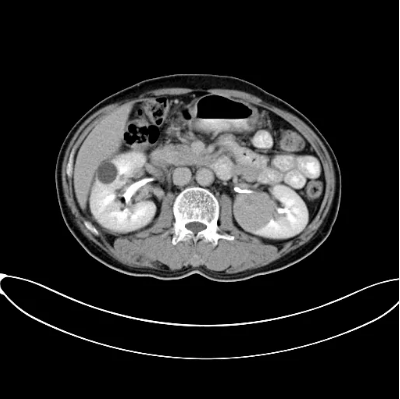

2017年9月29日,从CT影像看到右肾情况更为严重。为减缓肿瘤增长的速度,专家进行商议后,最终决定由牛立志教授主刀为安图叔叔进行了右肾肿瘤冷冻消融术。手术开始后,牛立志教授在CT和超声引导下,同时使用两根冷冻针固定病灶,精准灭活肿瘤;术后很成功无不良反应。术后一周进行第二次双肾肿瘤冷冻消融术。安图叔叔儿子笑道:“当时真的很紧张,医生劝慰我无须担心,都交给他们,我们都很清楚知道父亲的病情,真的很感谢也很庆幸我父亲遇到复大的医护人员,免受开刀之痛。住院期间医护人员很尽心尽力的照顾父亲,手术的成功离不开他们的辛劳付出。”

冷冻治疗手术中